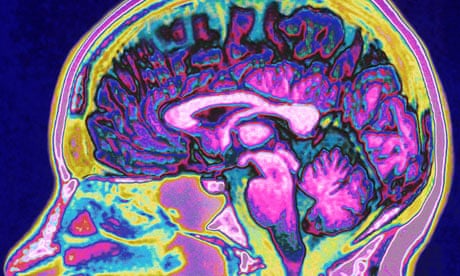

Watching The Human Brain Process Information Nieman Reports

Cortical Colouring In What Does Your Brain Do With Black And White

The Brain On Lsd Revealed First Scans Show How The Drug Affects The

513 Best Brain Imaging Research Images The Brain Psicologia